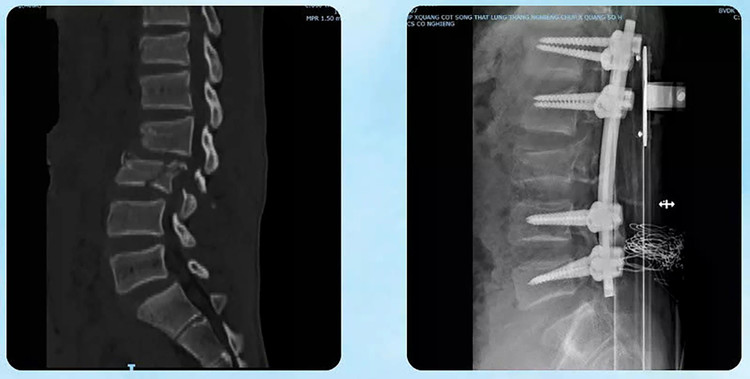

Nhờ sự phối hợp nhịp nhàng giữa các khoa Hồi sức cấp cứu, Ngoại Tổng hợp, Ngoại Thần kinh, Ngoại Chấn thương - Bỏng, áp dụng những kỹ thuật cao để can thiệp kịp thời và điều trị tích cực. Sau gần một tháng bệnh nhân đã hồi phục nhanh, tỉnh táo, chức năng vận động cải thiện rõ rệt; vượt qua giai đoạn nguy kịch một cách ngoạn mục.

Bệnh nhân đã hồi phục ngoạn mục - Ảnh BVCC

Lãnh đạo Bệnh viện Đa khoa tỉnh Quảng Trị cho biết, nhờ sự phối hợp chặt chẽ giữa các khoa chuyên môn cùng việc áp dụng kỹ thuật cao, bệnh nhân vượt qua giai đoạn nguy kịch.

Khi nam sinh có thể ngồi dậy và mỉm cười trở lại, đó không chỉ là thành quả của y học mà còn là nguồn động viên lớn đối với đội ngũ y bác sĩ nỗ lực không ngừng để giành lại sự sống cho bệnh nhân.